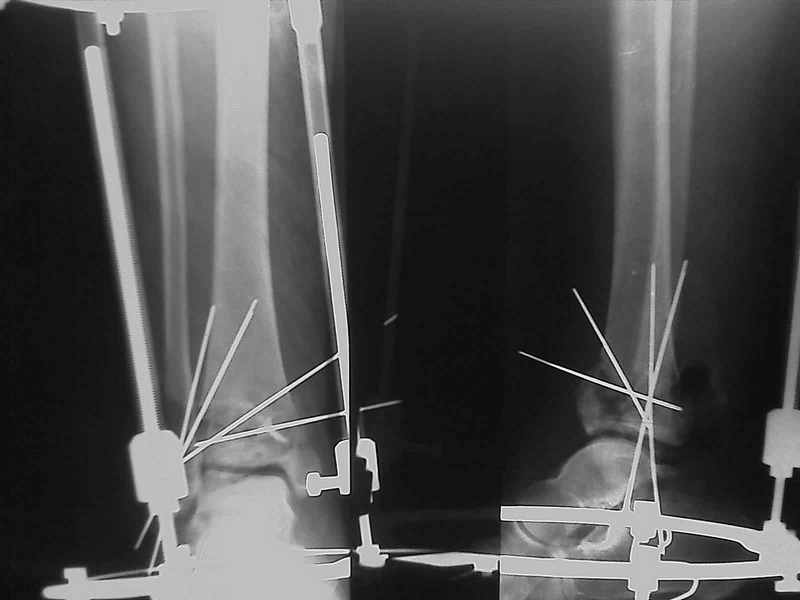

Снова приветствую вас, коллеги. К моменту вступления в обсуждение аксакалов, операция была, увы, выполнена(31.10.07.) Начали с доступа к наружной лодыжке, произвели ее фиксацию спицами, развернули кусок заднего края, наложили дистрактор, затем произвели дистракцию, фиксацию спицами дистального эпиметафиза б/бк,Рентгено-контроль. синтез наружной лодыжки 1/3пластиной. из двух коротких разрезов сформирован канал под медиальную тибиальную пластину LCP. Края ран ушиты без натяжения. Прочувствовать жесткость фиксации винтами с угловой стабильностью не удалось, поэтому дистрактор оставлен на энное время.

На представленных R-снимках не окончательный вид после остеосинтеза. Дистальная опора давила на стопу, пришлось ее сместить проксимально, в рез-те чего, она закрыла щель сустава, последние снимки не информативны.